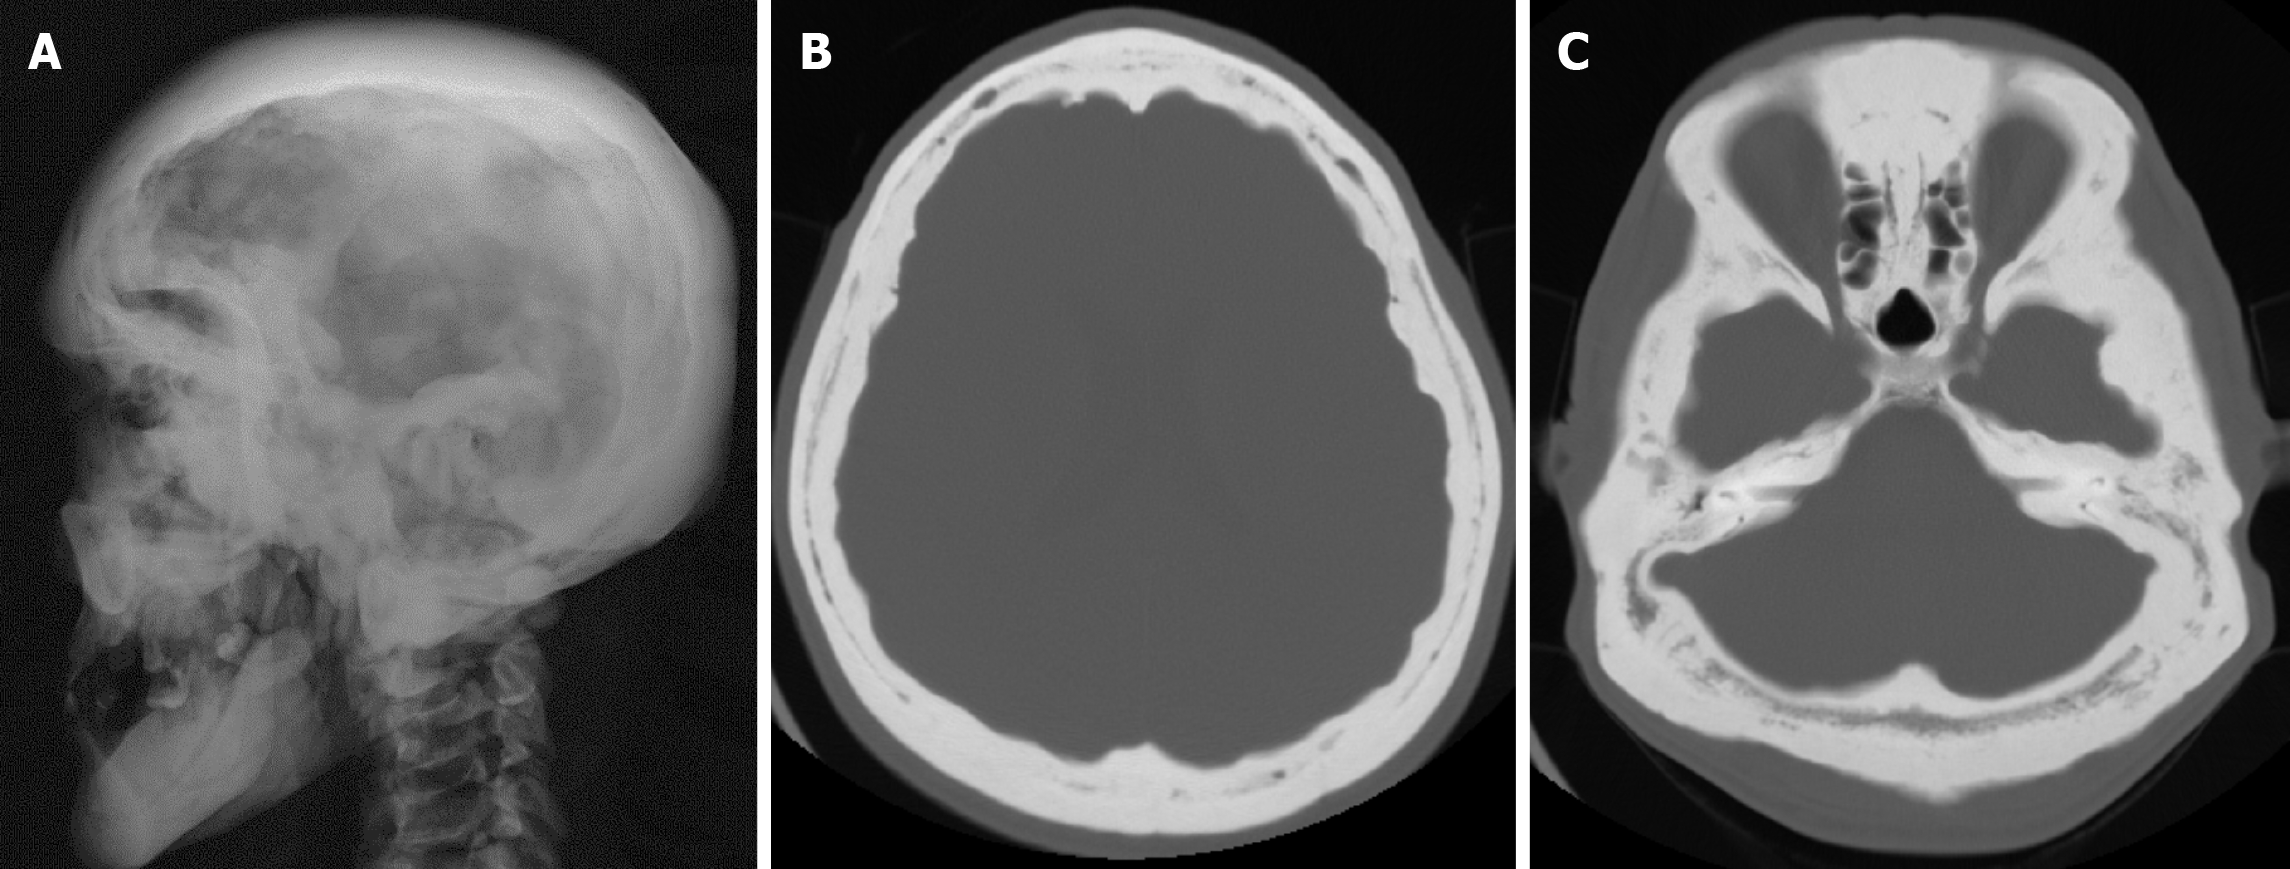

Arachnoid granulations (Pacchionian granulations) are cerebrospinal fluid-filled projections that extend from the subarachnoid space through openings in the dura into the venous sinuses and can be seen macroscopically. Their incidence varies from 0.3% to 55%. Arachnoid granulations are usually seen in millimeter dimensions, but may grow to fill the dural sinuses or arch the inner table[11]. In addition, intraosseous arachnoid granulations can sometimes extend to the inner table of the bone, causing scalloping, remodeling or bone erosion of the inner table[12]. The prevalence of arachnoid granulations increases with age, but there is no difference in gender distribution. Arachnoid granulations with a slight left hemispheric predominance are found in the dural venous sinuses, most frequently in the transverse sinuses and especially in the middle or lateral parts. The second most common location is the superior sagittal sinus, but they can be found anywhere in the dural venous sinuses. Arachnoid granulations are usually detected incidentally. If they fill and expand the dural sinuses, causing partial sinus obstruction, they may cause symptoms of increased intracranial pressure due to venous hypertension. They are usually associated with headaches. Arachnoid granulations may be seen as radiolucent areas on plain radiography of the skull or may cause compression on the inner table of the skull. On CT imaging, arachnoid granulations can be seen as sharply demarcated, hypodense structures in close relation to the dural venous sinus. On MRI, they usually show hyperintense signal on T2-weighted images and hypointense or isointense signal on T1-weighted images compared to brain parenchyma (Figure 1). On CT angiography, MR angiography or catheter angiography imaging, arachnoid granulations appear as oval or round filling defects in the dural venous sinuses during the venous phase[11]. Recent advances in radiology have made it possible to identify brain herniations into the arachnoid granulation by improving image quality with higher resolution and thinner slice three-dimensional T1-weighted and T2-weighted MRI sequences (Figure 2). Brain herniation into the arachnoid granulation is rare in the literature, and the incidence of brain herniation into the calvarial or dural sinuses has been reported to be 0.32%[13]. Arachnoid granulations may be confused with pathological processes in the dural venous sinuses[11]. In the differential diagnosis of arachnoid granulations, venous sinus thrombosis, dural-based tumors, or structures such as septa and fat that may cause filling defects in the dural venous sinuses should be considered[12]. Dural sinus thrombosis usually fills an entire sinus segment or several sinuses and may extend to the cortical veins, whereas arachnoid granulations appear as focal and well-defined defects. Fresh thrombus in the dural sinuses are hyperdense on CT and hyperintense on T1-weighted MRI. Differential tumor diagnosis can be made based on its shape, lack of contrast enhancement and diffusion restriction[11].

The transcalvarial venous channels are the openings in the calvarium that connect the dural venous sinuses to the extracranial veins via emissary veins. They are usually seen as serpentine or linear lucencies with sclerotic margins along the skull, and when these vessels are dilated they are known as venous lakes. Venous lakes are sometimes confused with fractures or sutures[14]. Venous lakes are present in about 15% of patients and are not associated with age or gender[15]. Venous lakes appear on CT as round or oval lucencies at the level of the skull base (Figure 3). On MRI, they show medium or low signal intensity on T1-weighted images, high signal on T2-weighted images, and significant contrast enhancement is seen in contrast-enhanced series[14]. It is important to distinguish venous structures from metastases. Metastases often show restricted diffusion within the lesion due to high cellularity. In addition, metastases may show increased blood flow within the lesion. Metastases often invade adjacent tissues[15].